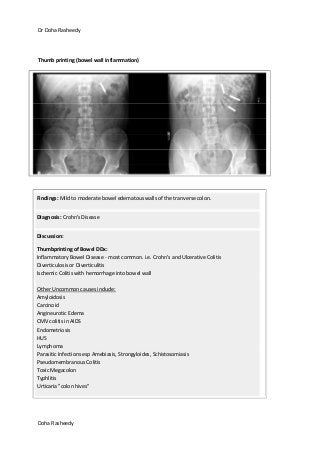

Thumb printing (bowel wall inflammation)

Findings: Mild to moderate bowel edematous walls of the tranverse colon.

Diagnosis: Crohn's Disease

Discussion:

Thumbprinting of Bowel DDx:

Inflammatory Bowel Disease - most common. i.e. Crohn's and Ulcerative Colitis

Diverticulosis or Diverticulitis

Ischemic Colitis with hemorrhage into bowel wall

Other Uncommon causes include:

Amyloidosis

Carcinoid

Angineurotic Edema

CMV colitis in AIDS

Endometriosis

HUS

Lymphoma

Parasitic Infections esp Amebiasis, Strongyloides, Schistosomiasis

Pseudomembranous Colitis

Toxic Megacolon

Typhlitis

Urticaria "colon hives"